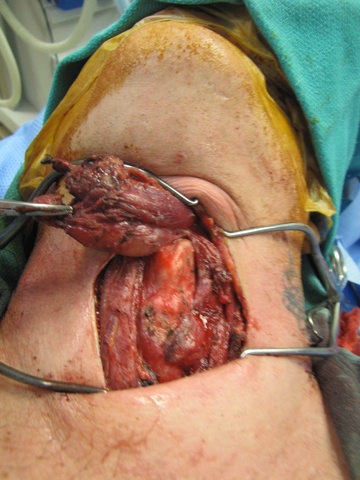

The hyoid bone was identified with preservation of soft tissue about the central portion and isolation of the bone laterally. On the right side, just medial to the lesser cornua and used a Freer underneath to protect while we released the hyoid with the mighty bite. The left side was addressed in identical fashion, except that we were lateral to the lesser cornua. The dissection was carried superiorly with a cuff of muscle.

From above, surgeon reached into the mouth and palpated the foramen cecum with the left hand and arm protected with a sterile sleeve and second glove - placed to permit later removal from the contaminated oral cavity to permit continued sterile dissection in a sterile field. With anatomic control directed by palpation intra-orally with concurrent dissection of the open neck, clips were placed to mark the region of the undersurface of the base of tongue where the TGD cyst was to be severed. Final cuts with the bovie were similarly directed both by intra-oral palpation and extra-oral inspection.

Clinical Images